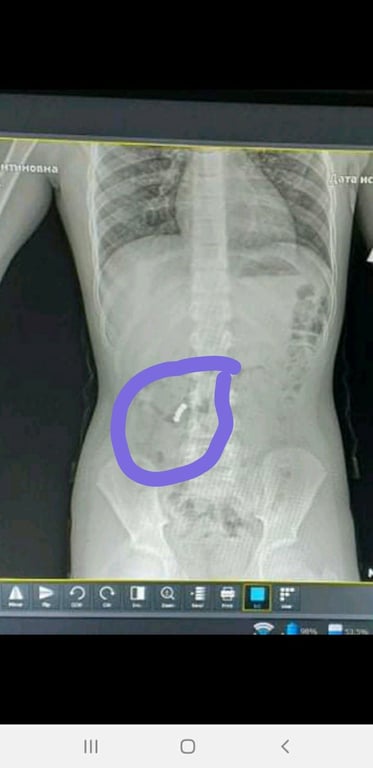

Зазначається, що дитина, яка навчається у четвертому класі, під час гри проковтнула магніти. Чотири магнітних кульки почали хімічну реакцію в організмі – почалися склеюватися внутрішні органи. Відомо, щоби витягнути магніти, дитині потрібна операція.